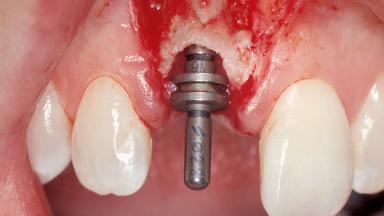

Immediate Placement of an Implant in a Maxillary Right Central Incisor Site

A 30-year-old female patient was referred to the office for the treatment of tooth 11. Her chief concern at the initial visit was to inquire, “Why is my tooth pink?” Upon clinical examination, it was determined that tooth 11 had a previous history of trauma and that the clinical crown had become noticeably pink in color as a result of internal resorption. This diagnosis was confirmed radiographically, indicating a large radiolucency involving the central and distal portions of the clinical crown. It was determined that restoration of this tooth was not possible, and that extraction was indicated. The presence of a mid-line diastema, which the patient wanted to reproduce, directed the treatment plan for tooth replacement utilizing a dental implant.

Type of Implants One-Piece|Reduced-Diameter

Bone Augmentation Horizontal|Simultaneous

Augmentation Materials Autogenous chips|Membrane